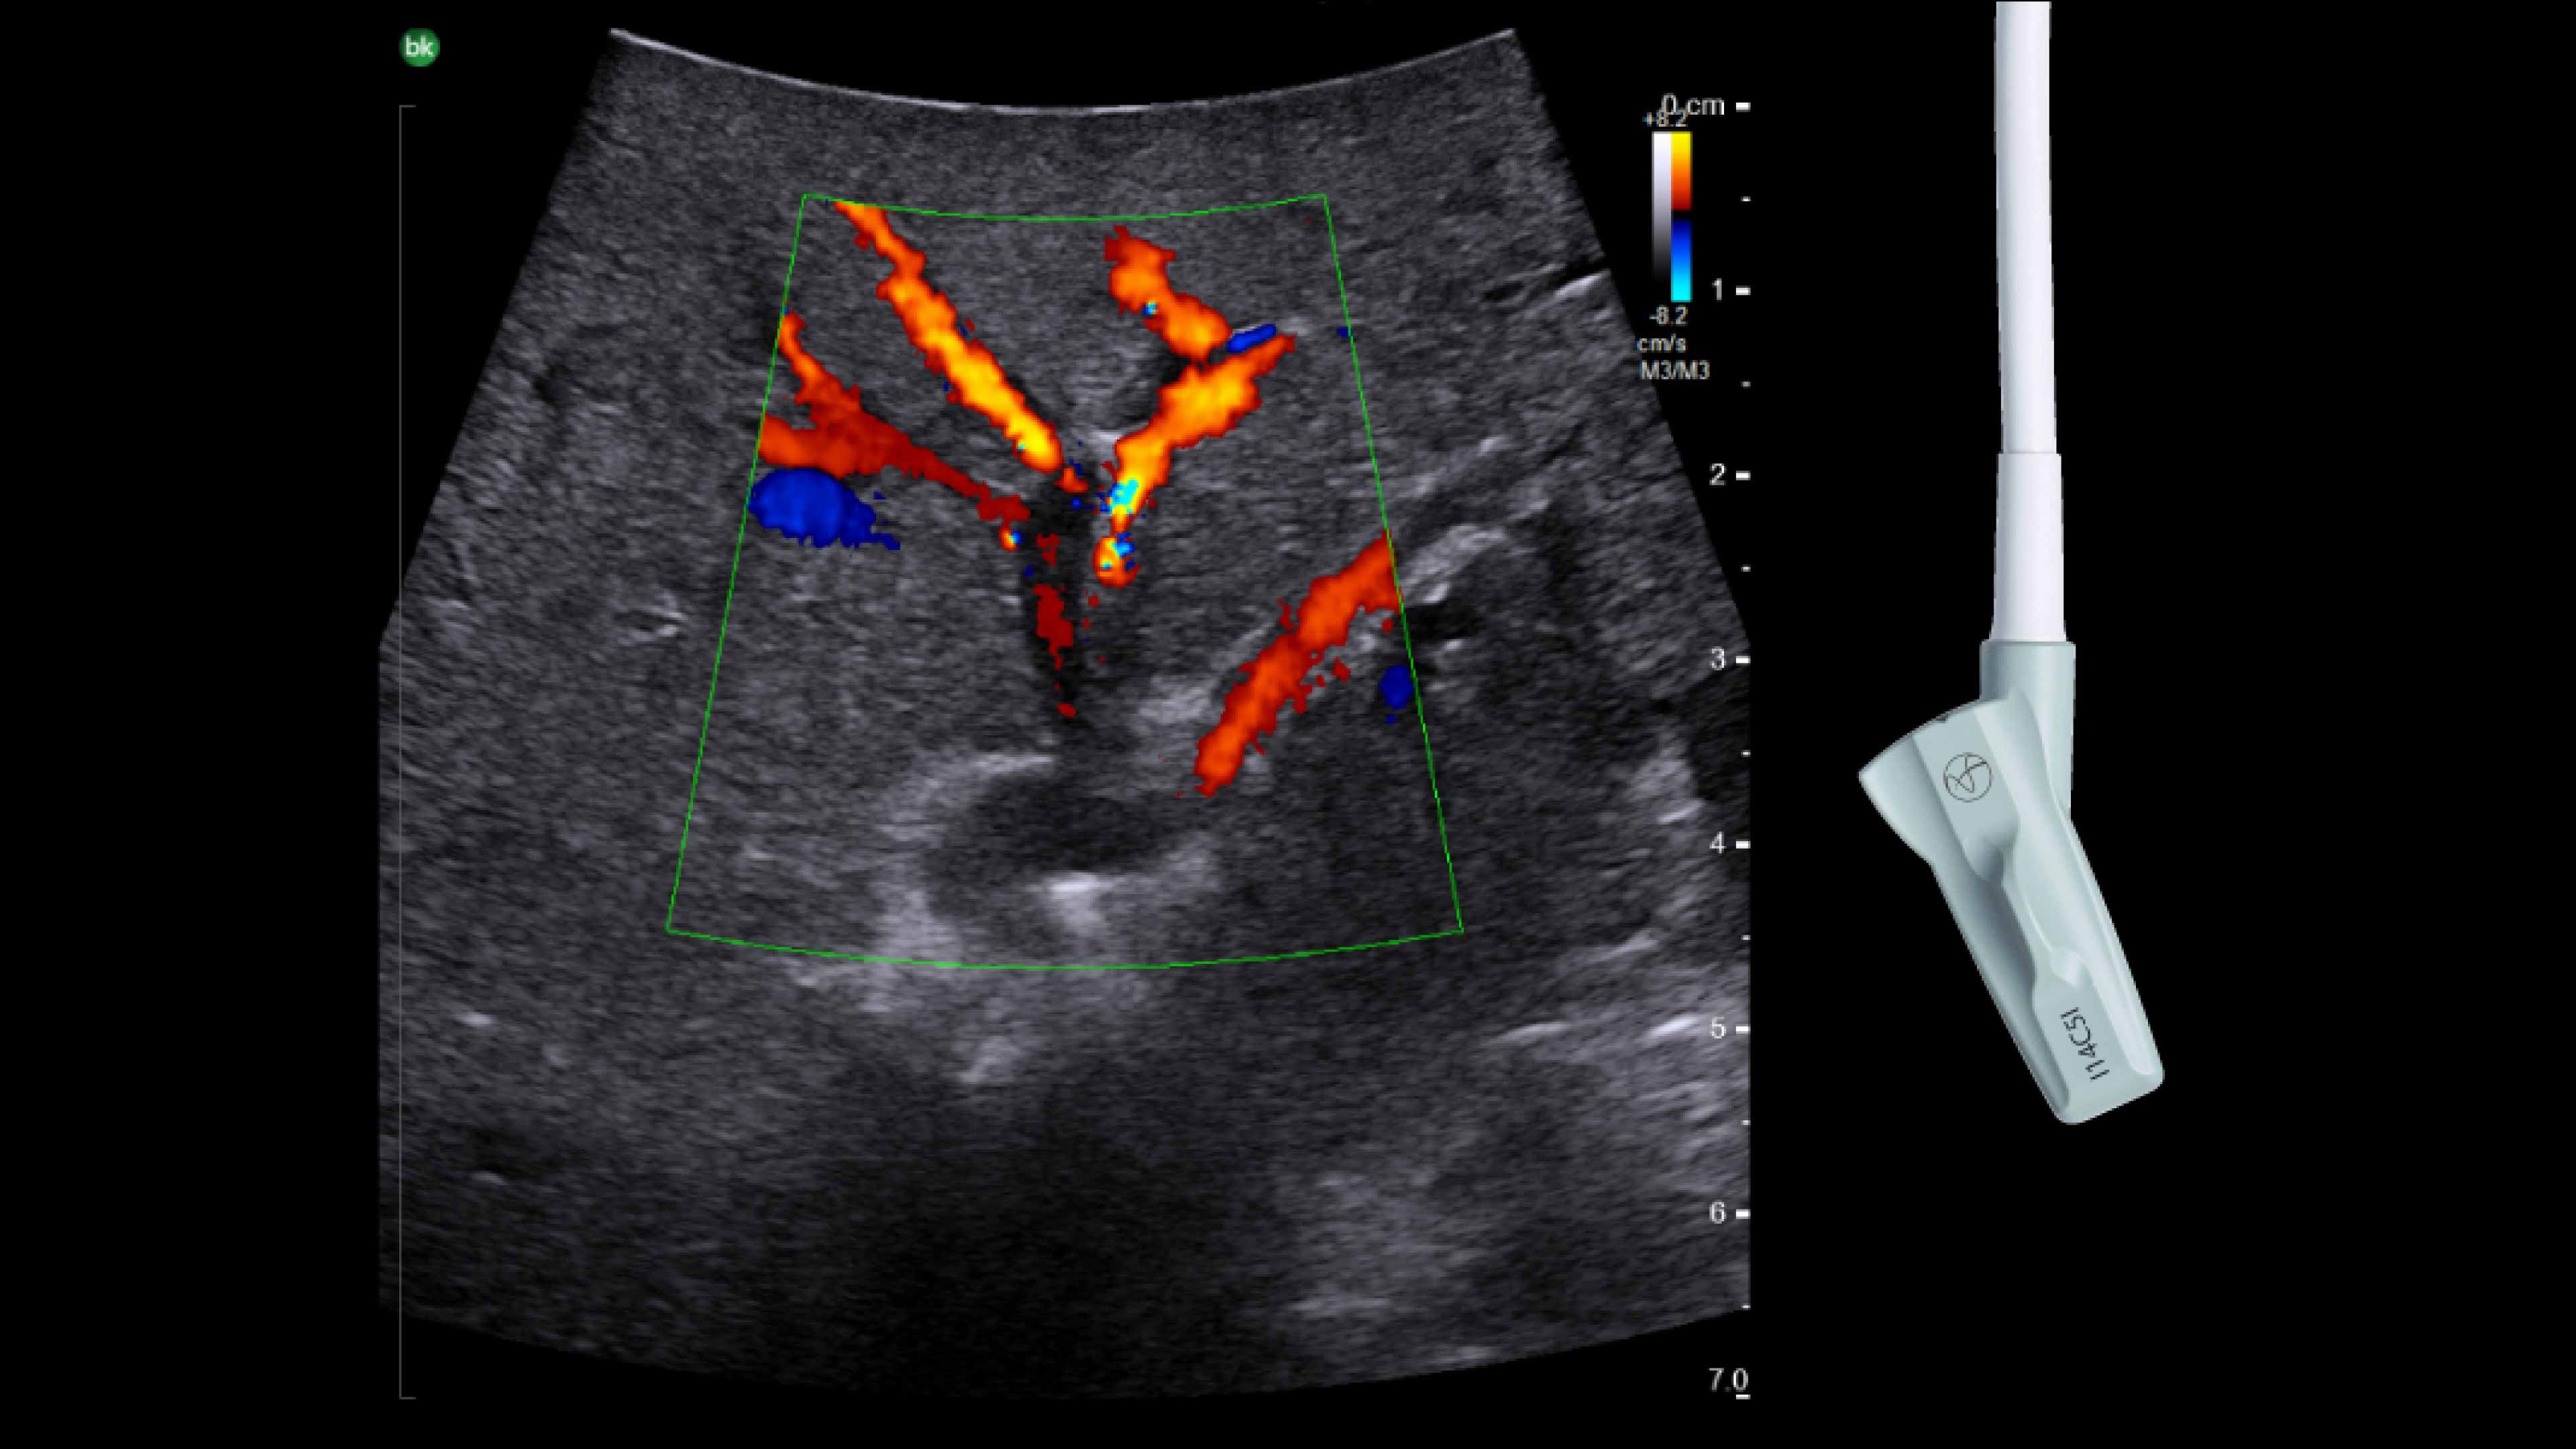

• iUS uses color flow doppler to help differentiate between vessels and ducts and is overall effective at imaging difficult cases such as inflammation or fibrosis .¹,⁴⁻⁶

Cholecystectomy ultrasound

Active imaging with real-time intraoperative ultrasound supports fast imaging of the biliary system and is non-radiating, helping you reduce radiation hazards to your patients and staff.

Imaging to guide cholecystectomies

Discover the clinical benefits of active imaging with intraoperative ultrasound for laparoscopic cholecystectomy procedures. Using bkActiv and the Advanced Laparoscopic Transducer, surgeons can visualize anatomy and monitor progress as many times as needed during the procedure.

iUS is beneficial for cholecystectomies due to its safety, quick and repeatable imaging capabilities and ability to detect choledocholithiasis and enable visualization of biliary tract anatomy.